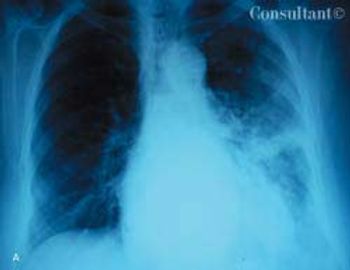

A 48-year-old woman was admitted to the hospital with deep venous thrombosis of the right leg. She had a history of non-Hodgkin lymphoma, which was in remission. The patient had been a heavy smoker for many years.